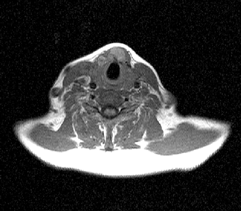

Исследования, проведенные нами в последние годы у 65 больных раком щитовидной железы, показали, что применение РКТ в сочетании с МРТ позволяет в высоком проценте случаев до операции иметь информацию о взаимоотношении распространенной опухоли щитовидной железы с окружающими анатомическими структурами (рис. 3, 4, 5).

Рисунок 4. МРТ: опухолевое поражение перешейка щитовидной железы